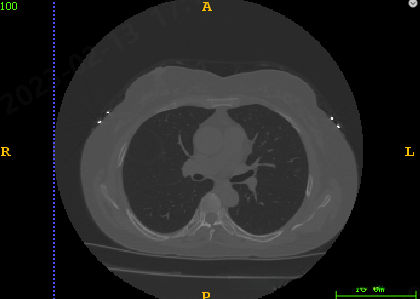

结果